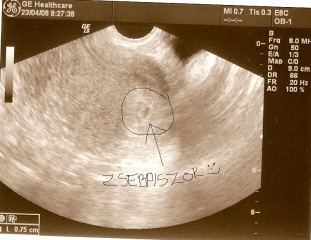

Bekarikáztam a picúrt, hogy könnyen megtalálható legyen :D

Kép

Édes kis Zsebpiszkotok van :P :P

Bessy: Gratula mégegyszer a kis petezsákhoz :) Jól kivehető a képen :)